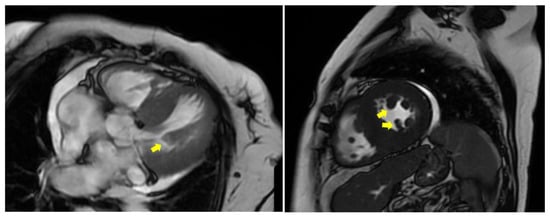

7.2. Hypertrophic (Obstructive) Cardiomyopathy